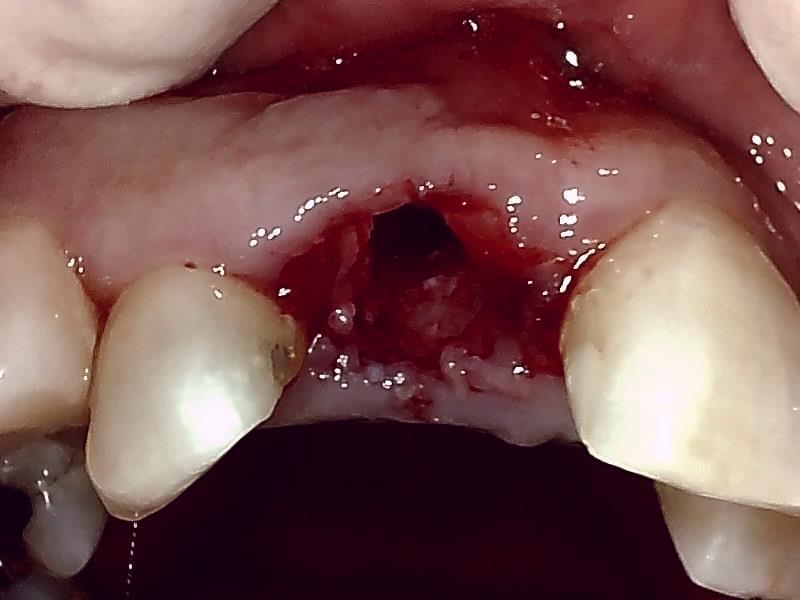

抜歯窩の状態

自家骨移植 GBR を施す。理想的な顎堤に築造する。